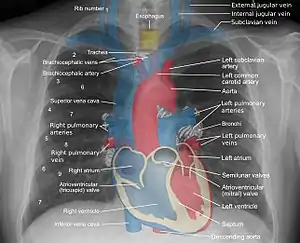

![]() A normal posteroanterior (PA) chest radiograph of someone without any signs of injury. Dx and Sin stand for "right" and "left" respectively. | |

A chest radiograph, called a chest X-ray (CXR), or chest film, is a projection radiograph of the chest used to diagnose conditions affecting the chest, its contents, and nearby structures. Chest radiographs are the most common film taken in medicine.

Landmarks

In the average person, the diaphragm should be intersected by the 5th to 7th anterior ribs at the mid-clavicular line, and 9 to 10 posterior ribs should be viewable on a normal PA inspiratory film. An increase in the number of viewable ribs implies hyperinflation, as can occur, for example, with obstructive lung disease or foreign body aspiration. A decrease implies hypoventilation, as can occur with restrictive lung disease, pleural effusions or atelectasis. Underexpansion can also cause interstitial markings due to parenchymal crowding, which can mimic the appearance of interstitial lung disease. Enlargement of the right descending pulmonary artery can indirectly reflect changes of pulmonary hypertension, with a size greater than 16 mm abnormal in men and 15 mm in women.[6]

Appropriate penetration of the film can be assessed by faint visualization of the thoracic spines and lung markings behind the heart. The right diaphragm is usually higher than the left, with the liver being situated beneath it in the abdomen. The minor fissure can sometimes be seen on the right as a thin horizontal line at the level of the fifth or sixth rib. Splaying of the carina can also suggest a tumor or process in the middle mediastinum or enlargement of the left atrium, with a normal angle of approximately 60 degrees. The right paratracheal stripe is also important to assess, as it can reflect a process in the posterior mediastinum, in particular the spine or paraspinal soft tissues; normally it should measure 3 mm or less. The left paratracheal stripe is more variable and only seen in 25% of normal patients on posteroanterior views.[7]

Localization of lesions or inflammatory and infectious processes can be difficult to discern on chest radiograph, but can be inferenced by silhouetting and the hilum overlay sign with adjacent structures. If either hemidiaphragm is blurred, for example, this suggests the lesion to be from the corresponding lower lobe. If the right heart border is blurred, than the pathology is likely in the right middle lobe, though a cavum deformity can also blur the right heard border due to indentation of the adjacent sternum. If the left heart border is blurred, this implies a process at the lingula.[8]